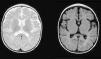

Diffuse and patchy signal abnormalities in white matter in both cerebral hemisphere, hyperintense in T2-weighted images. Enlarged subarachnoid space with frontotemporal predominance in both hemispheres, with widening of the interhemispheric fissure and increased ventricular size (in the absence of increased pressure), compatible with cortical and subcortical atrophy.

| Head MRI | Diffuse and patchy changes in WM intensity of both cerebral hemispheres, hyperintense on T2. Involvement of subcortical WM (sparing the U fibres) and periventricular WM | Generalised WM involvement with predominance of lobar WM including the subcortical U fibres of the frontal, temporal and occipital lobes, bilaterally and symmetrically, without cortical involvement | – |